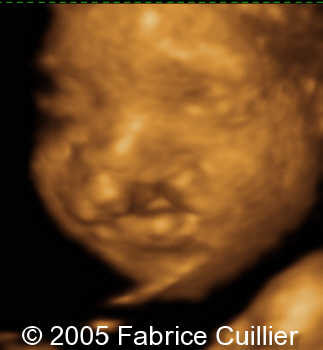

Cleft lip unilateral, 26 weeks

The following are the ultrasound images of a fetus with unilateral cleft lip, discovered at 26 weeks of gestation.

3D rendered images: